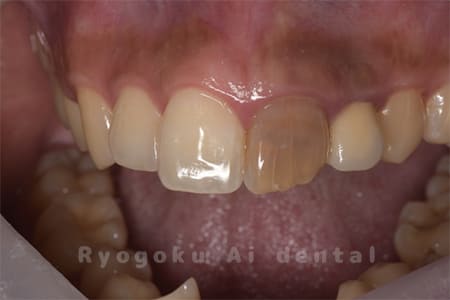

Case04

- 原因

- 失活による歯牙変色

- 治療内容

- ブリーチング+マイクロエンド+ダイレクトボンディング+ホワイトニング

- 治療費用

- 231,000円(ブリーチング55,000円+マイクロエンド77,000円+ダイレクトボンディング66,000円+ホワイトニング33,000円)

結婚式前に前歯を綺麗にしたいとのことでご来院された患者様です。根の状態も悪かったためマイクロスコープ下で根管治療を行い、ブリーチングの後にダイレクトボンディングで形態修正を行いました。